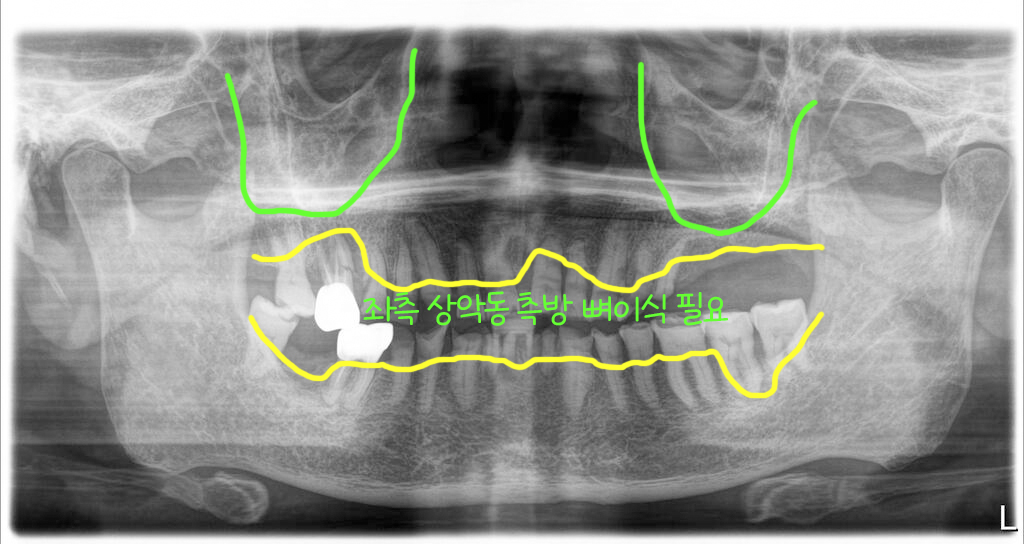

위쪽에 치아뿌리 염증이 심한 어금니 한개가 아래로 내려와 있었고, 위쪽 왼쪽(사진상으론 오른쪽) 어금니 부위에는 이미 치아가 빠져있고 뼈가 너무 없어 상악동 측방 뼈이식이 필요한 상태였어요.

좌측 상악동뼈이식과 함께

상악은 모두 발치 후 임플란트를 12개 심었고, 좌측 상악동은 측방접근 뼈이식을 하면서 식립을 했습니다. 상악동거상술과 함께 식립된 임플란트는 고정이 부족해서 힐링을 끼워두고 임시치아에 적용하지 않았어요.